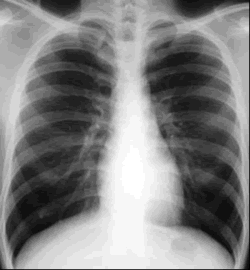

Tuberculosis (TB)

Articles on Tuberculosis

Tuberculosis (TB): An Overview from the U.S. Centers for Disease Control and Prevention